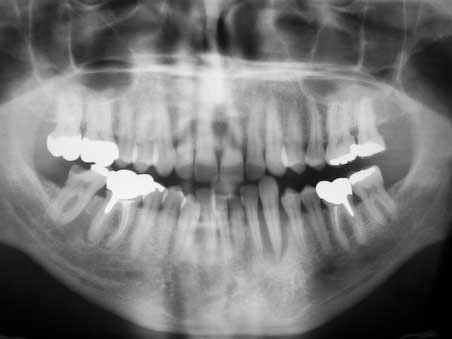

Hoffnungsloser Eckzahn 1

Veröffentlicht 1. Februar 2009 am 452 × 339 in Hoffnungsloser Eckzahn